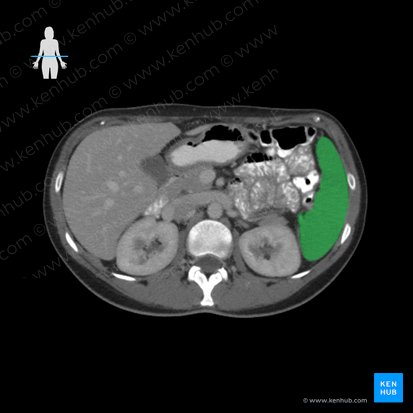

Die charakteristische Form und eine intakte Kapsel sind die wichtigsten Merkmale der Milz auf einem Computertomogramm. Die Größe der Milz ist variabel, sodass nicht die Größenzunahme sondern eine Veränderung hinweisgebend auf eine Milzvergrößerung ist. Normalerweise besitzt die Milz eine konkave, also nach innen gewölbte viszerale Oberfläche (Facies visceralis). Bei einer pathologisch vergrößerten Milz erscheint diese Oberfläche hingegen konvex und somit nach außen gewölbt.